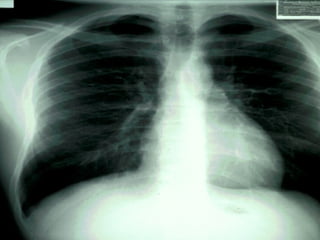

Note the  base  and the  apex  of the lungs.  Also note that the left lung only has two  lobes , while the right lung has three.

The  lungs  are large, spongy, paired organs in the thoracic cavity

All structures of the respiratory tract beyond the primary bronchi are contained in the lungs.  Note the  right lung  has  three lobes  while the  left lung  has only  two lobes  because of the space taken up by the heart on that side.